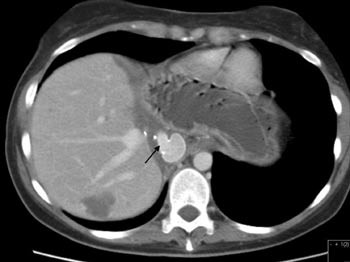

Pasient 2. 29 år gammel kvinne som de siste tre år hadde merket økende bukomfang og ubehag i abdomen. Hun hadde gjentatte ganger konsultert lege for dette før hun ble innlagt i lokalsykehus til utredning for anemi. Det ble der konstatert at pasienten hadde en meget stor levertumor, hvorpå hun ble overflyttet til Rikshospitalet. Hun hadde da et bukomfang som ved langtkommet graviditet. Nedre kant av tumor kunne palperes nedenfor umbilicus. CT (fig 5) viste at det dreide seg om en ekstremt stor levertumor, et sannsynlig hemangiom, som inntok hele venstre leverlapp, inkludert segment 4. Høyre leverlapp var flatklemt ut mot flanken. Den retrohepatiske del av v. cava var tilsynelatende okkludert, og et utstrakt nett av kollateraler ble påvist. Preoperative laboratorieprøver er vist i e-tabell 2.

Operasjonen ble utført 18.11. 2002. Etter konstruksjon av veno-venøs bypass ble den ekstremt forstørrede leveren (fig 6) eksplantert sammen med tilhørende del av v. cava. På sidebordet ble så hele neoplasmet ekstirpert (e-fig 7). Den resterende del av leveren (segment 5 – 8) ble deretter lagt tilbake i pasienten og revaskularisert som skissert i figur 8. Pasientens v. cava var i mellomtiden blitt erstattet av en ca. 10 cm lang goretexprotese med diameter 22 mm. En preoperativt diagnostisert, men ubehandlet stenose i a. coeliaca antas å ha vært en disponerende årsak til trombosering i leverarterien. Den ble påvist ved ultralydkontroll neste morgen.